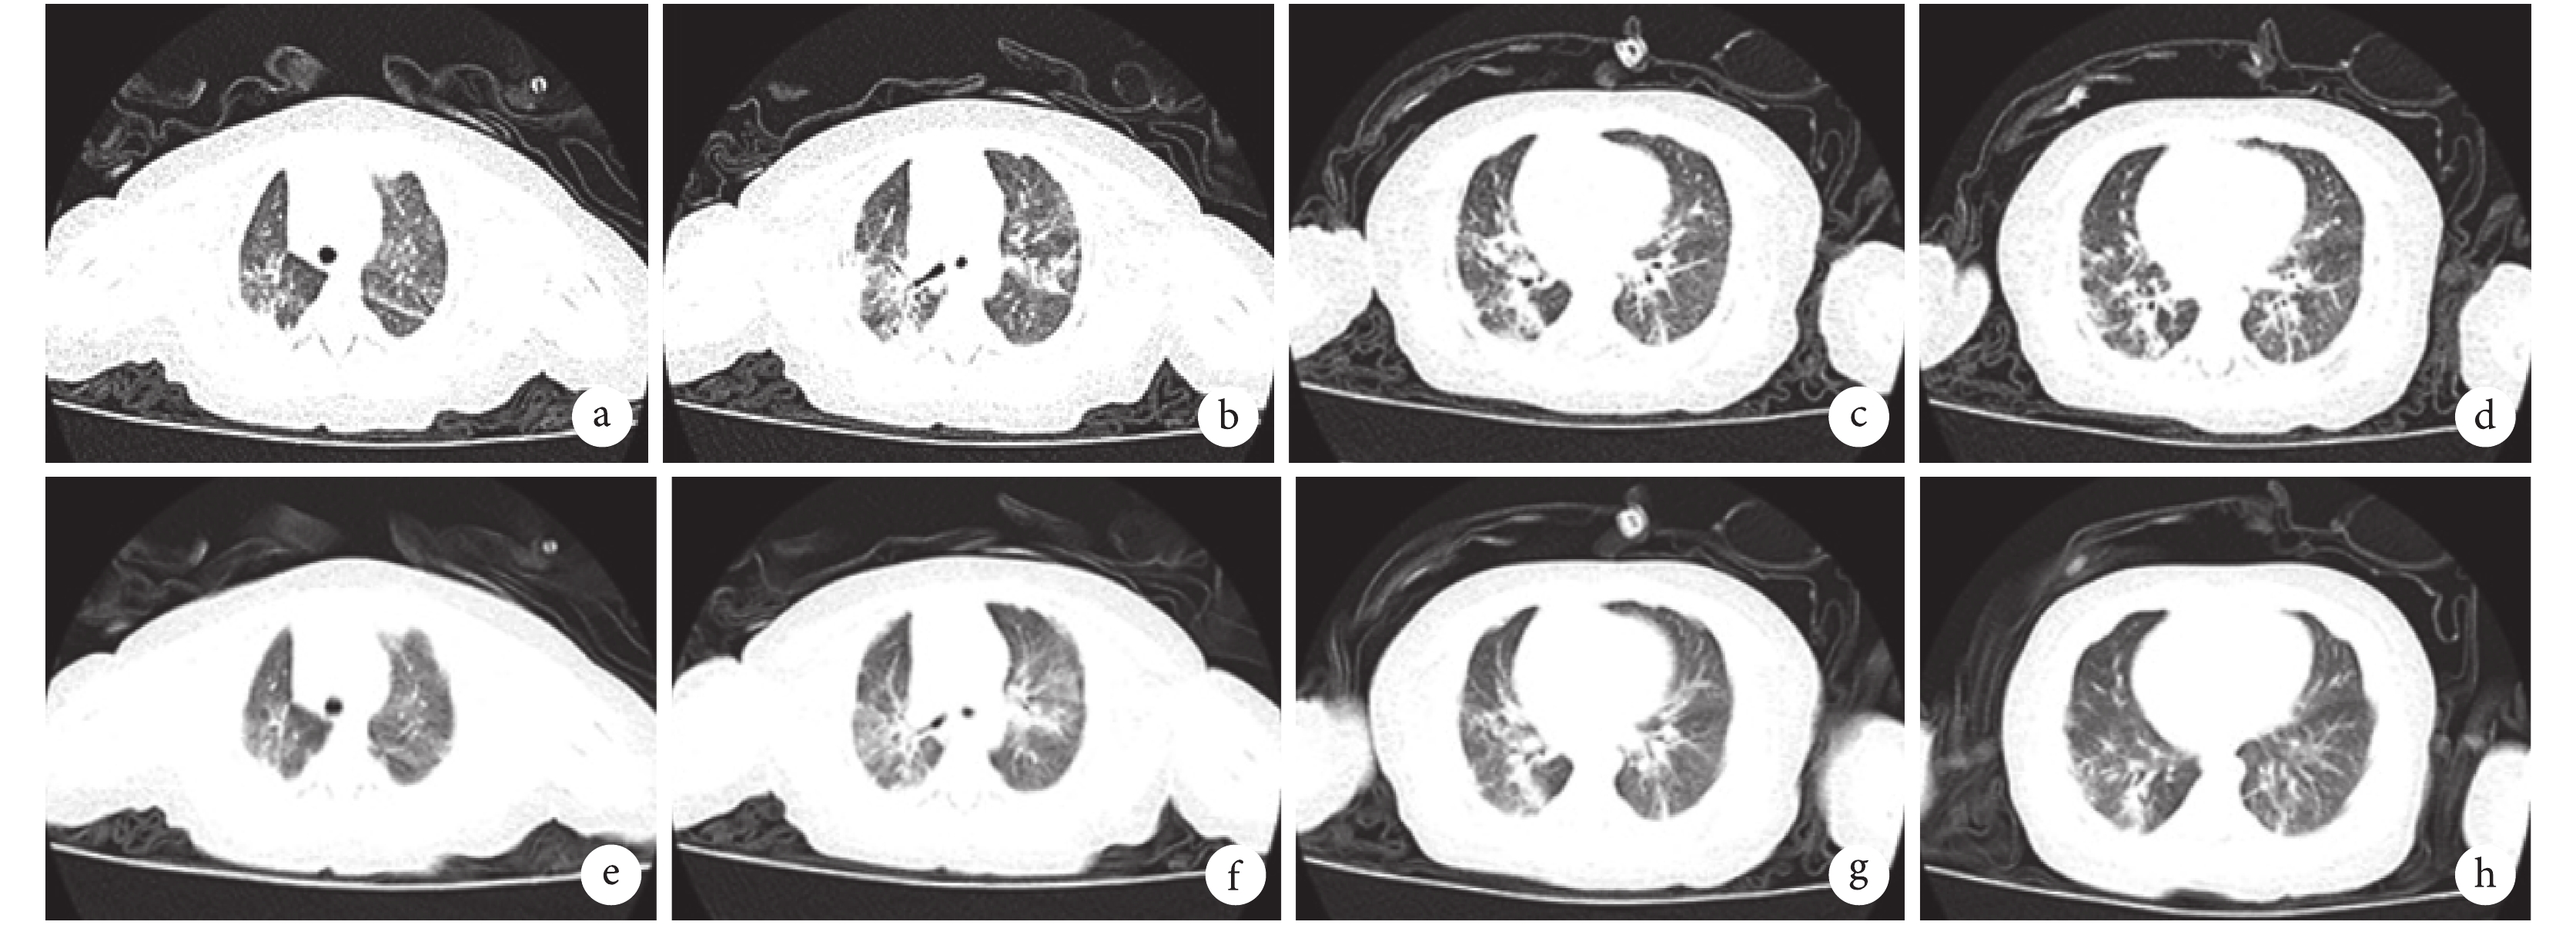

輔助檢查:血氣分析酸堿度 7.33,乳酸 2.3 mmol/L,二氧化碳分壓 50 mm Hg,氧分壓 198 mm Hg,細胞內堿剩余 0.5 mmol/L,細胞外堿剩余 0.4 mmol/L,實際碳酸氫根 26.4 mmol/L,標準碳酸氫根 25.3 mmol/L。血液分析、肝腎功、免疫球蛋白、細胞免疫、C 反應蛋白、真菌抗原檢測未見明顯異常。呼吸道病原體檢測 EB 病毒 IgM 抗體定性陰性,肺炎支原體抗體定量陰性,11 項呼吸道病原體陰性,TORCH 陰性。呼出氣一氧化氮(FeNO)濃度 9 ppb。痰培養、血培養陰性。肺功能檢查報告(潮氣分析):達峰時間比:17%,降低。達峰容積比:21.5%,降低;吸呼比:0.59,降低。呼氣時間明顯延長。提示:氣道阻力增加,潮氣通氣功能降低。胸部 CT + 氣道重建:雙肺可見斑片影及磨玻璃影,以斑片影為主,并見散在條索狀影,呈網格樣改變,肺組織含氣不均勻,見散在透光度增大區(圖 1a~d)。

a~d. 2019 年 4 月,雙肺可見斑片影及磨玻璃影,以斑片影為主,并見散在條索狀影,呈網格樣改變,肺組織含氣不均勻,見散在透光度增大區;e~f. 2019 年 5 月,較前期斑片影及磨玻璃影吸收好轉,只見少量透光度增加區。

隨訪:出院后 1 個月復查患兒呼吸平穩,精神飲食好,體重增長可。復查胸部 CT:較前片斑片影及磨玻璃影吸收好轉,只見少量透光度增加區(圖 1e~h)。復查肺功能(潮氣分析):達峰時間比 21.1%,降低;達峰容積比 24%,降低;吸呼比 0.72,正常。提示:氣道阻力增加,潮氣通氣功能降低。FeNO 為 28 ppb。臨床考慮治療有效,繼續予以阿奇霉素、潑尼松口服、輔舒酮霧化治療。出院后 6 個月再次追蹤患兒,無氣促及咳嗽,精神飲食好,體重增長可。復查胸部 CT 炎癥基本吸收,復查免疫球蛋白及細胞免疫仍未見明顯異常,逐漸停用阿奇霉素及潑尼松。目前患兒 2 歲,未見癥狀復發。